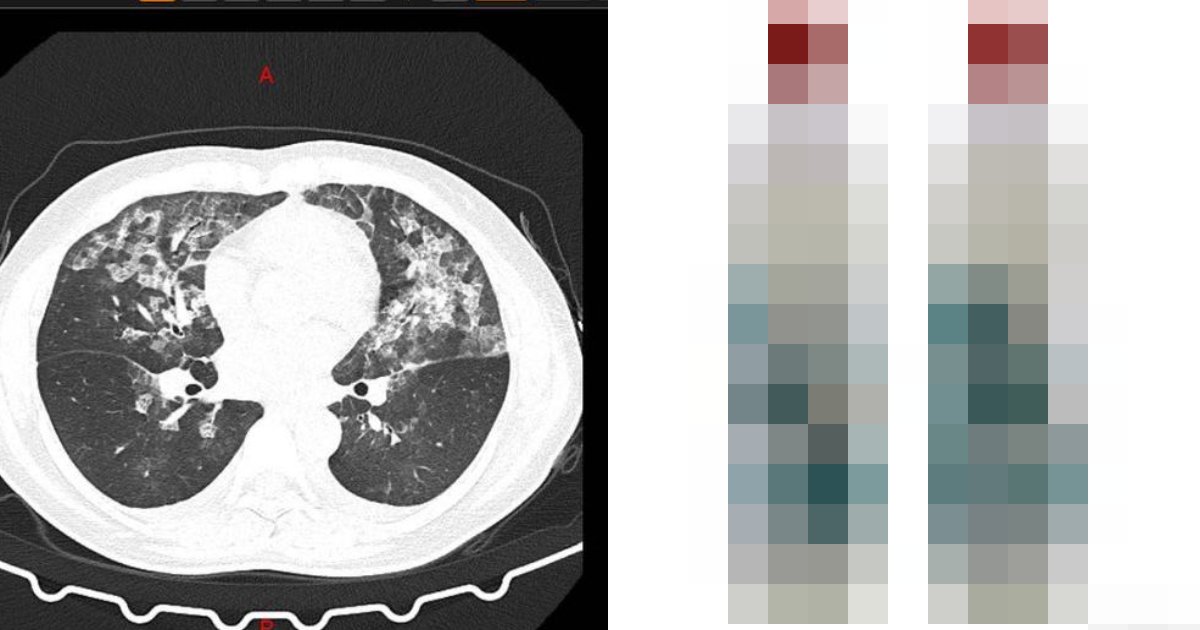

最近、中国河南省鄭州の病院に 女性2人がめまいや脱力感などを訴え入院しました。新型コロナウイルスへの警戒が続く中、病院はCTスキャンによる検査を行ったところ、患者の肺からすりガラス状の白い影が見つかりました。

それはまさに新型コロナ肺炎の特徴と一致するものでした。

しかし、患者は武漢に行ったこともなく、近所に感染確認患者もいないという。CT写真の白い影は新型コロナ肺炎のそれとよく似ているものの、過去の接触歴、症状、血液検査いずれも新型コロナ肺炎のものとは合致せず、医師らを悩ませました。

このため医師らは、2人の女性に対し、新型コロナウイルスではなく、長時間にわたり高濃度の「84消毒液」を吸い込んだことによる“アレルギー性肺胞炎”との診断を下しました。